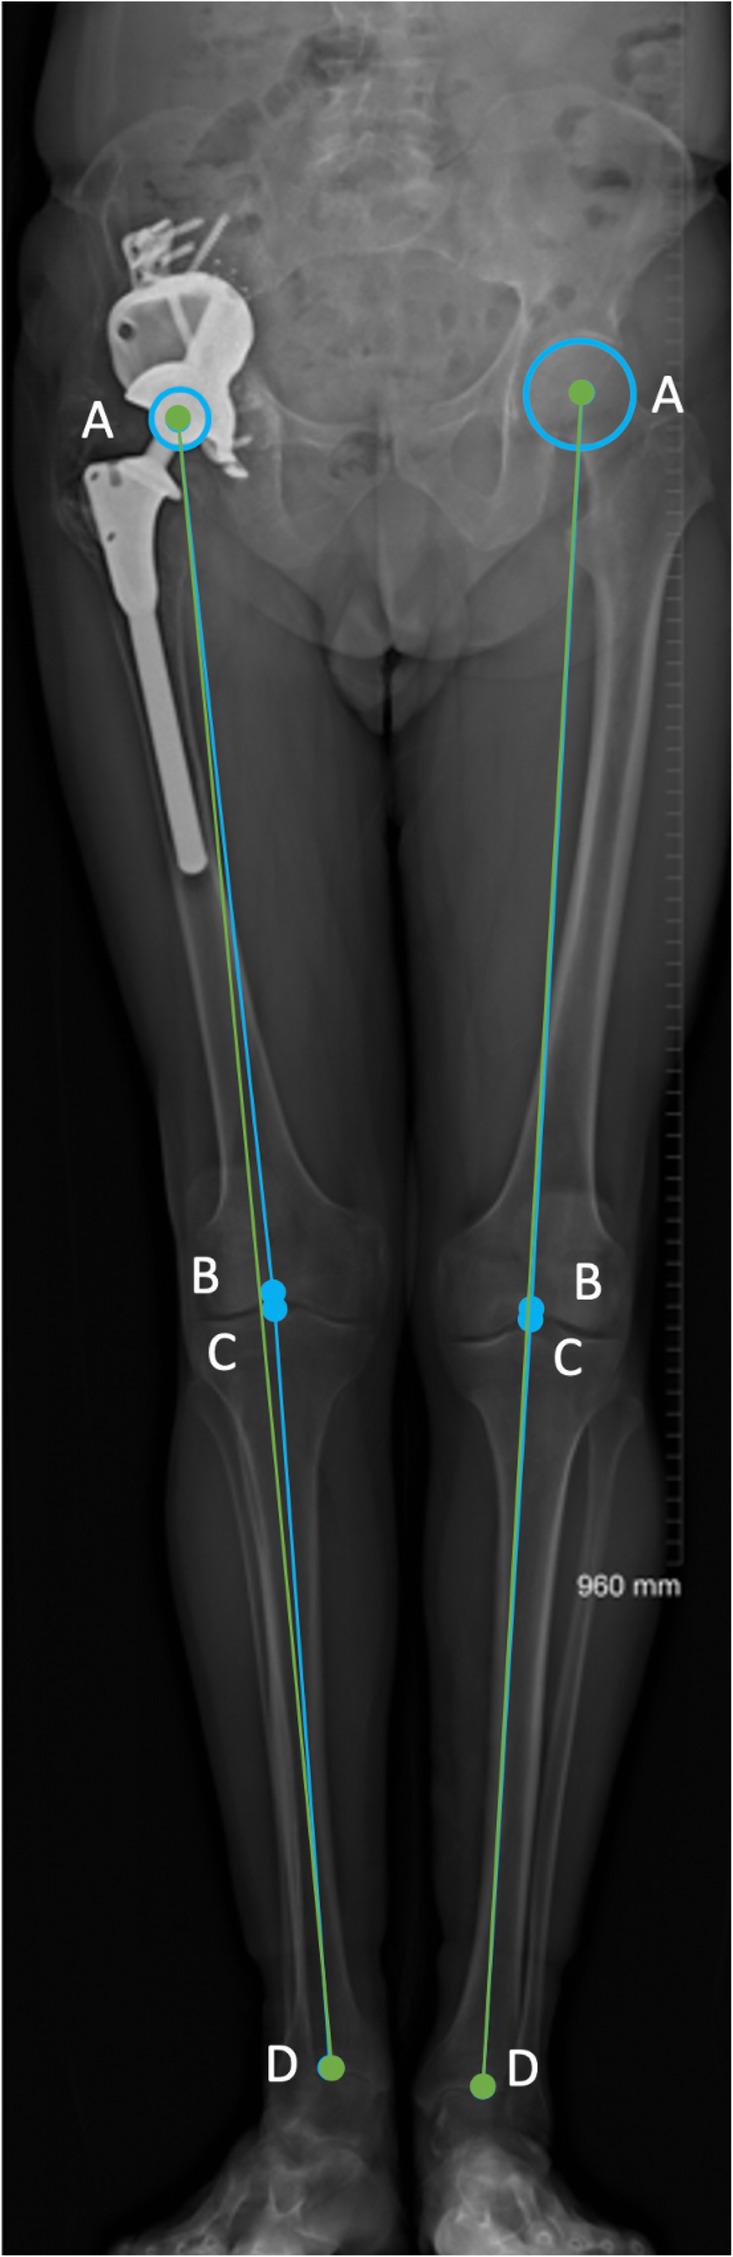

This was a prospective case study of 25 patients. We report the analysis of pre-operative LL status and planned LL restoration measured on CT, in relation to the achieved LL measured post-operatively in functional, weight bearing position. Our primary objective was the assessment of restoration of CoR as well as the anatomical and functional LL using biplanar full-length standing low-dose radiographs; our secondary objective was to evaluate the clinical outcome.

Pre-operative intra-pelvic discrepancy between right and left leg was a mean of 28 mm (SD 17.99, min = 3, max = 60 mm). Post-operatively, the difference between right and left vertical femoral offset (VFO), or CoR discrepancy, was of 7.4 mm on average, significantly different from the functional LL discrepancy (median = 15 mm), p = 0.0024. Anatomical LLD was a median of 15 mm. In one case there was transient foot drop, one dislocation occurred 6 months post-operatively and was treated by closed reduction, none of the patients had had revision surgery at the time of writing. Mean oxford hip score at latest follow up was 32.1/48.

This is the first study to investigate limb length discrepancy in functional position after reconstruction of large acetabular defects. We observed that VFO is not an optimal surrogate for LL when there is significant bone loss leading to length inequality, fixed flexion of the knee and abduction deformity.

这是一项对25例患者的前瞻性病例研究。我们报告了术前下肢长度状态分析以及在CT上测量的计划下肢长度恢复情况,并与术后在功能负重位测量的实际下肢长度相关。我们的主要目标是使用双平面全长站立低剂量X线片评估旋转中心的恢复以及解剖学和功能性下肢长度;次要目标是评估临床结果。

术前左右下肢骨盆内差异平均为28毫米(标准差17.99,最小值 = 3,最大值 = 60毫米)。术后,左右股骨垂直偏移(VFO)差异,即旋转中心差异,平均为7.4毫米,与功能性下肢长度差异(中位数 = 15毫米)显著不同,p = 0.0024。解剖学下肢长度差异中位数为15毫米。1例出现短暂性足下垂,1例术后6个月发生脱位,经闭合复位治疗,在撰写本文时无患者进行翻修手术。最新随访时牛津髋关节评分平均为32.1/48。

这是第一项研究大髋臼缺损重建后功能位下肢长度差异的研究。我们观察到,当存在导致长度不等的大量骨质丢失、膝关节固定屈曲和外展畸形时,VFO并非下肢长度的最佳替代指标。